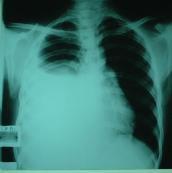

盡管目前許多強(qiáng)有力的抗生素在臨床應(yīng)用,肺炎仍然是最常見的疾病之一。在美國,肺炎伴胸腔積液位居胸腔積液病因的第2位,滲出性胸腔積液病因的第1位。大多數(shù)類肺炎性胸腔積液通過有效的抗生素治療而積液可以自行吸收。但是,約10%的胸腔積液需要手術(shù)干預(yù)。